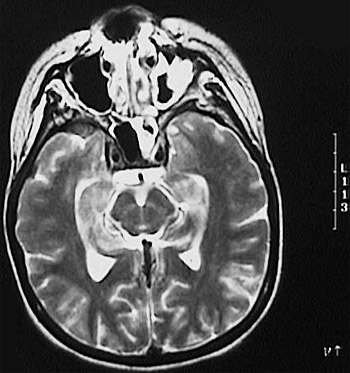

This MRI scan of the head reveals an irregular enhancing area of mucormycosis on the left.